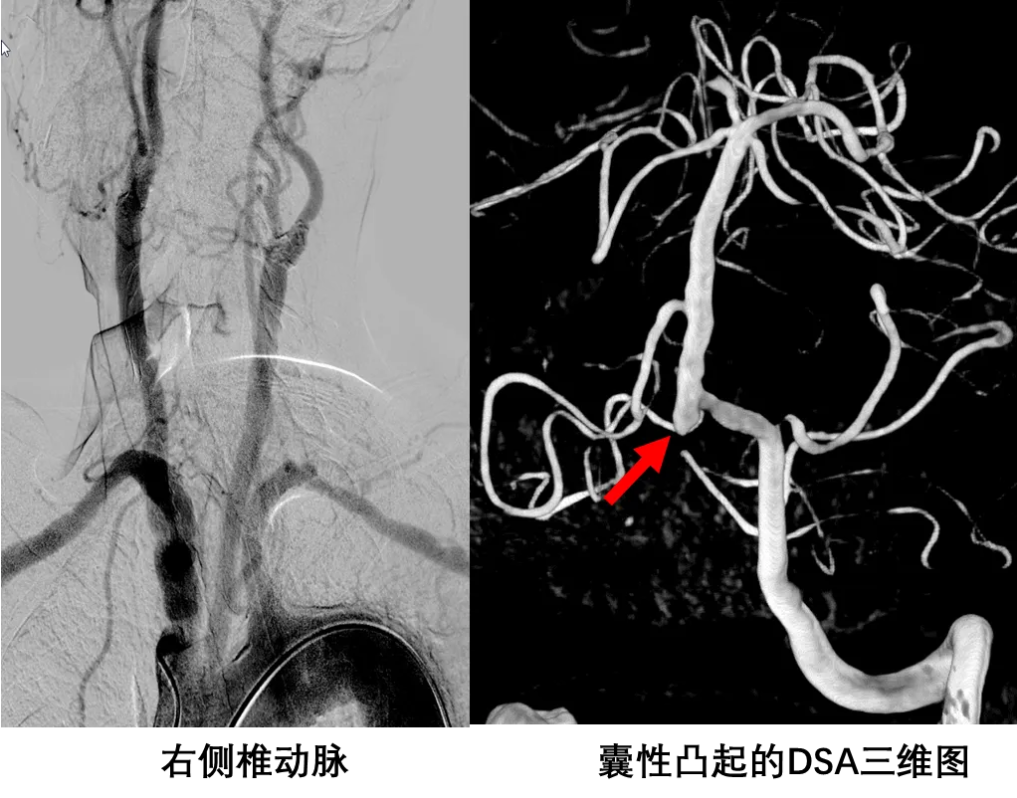

四、DSA检查

五、磁共振亮血MRA

HMRA与CTA,DSA结果一致,无法提供更多的信息。